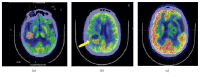

Primary Central Nervous System Lymphoma (PCNSL) is a rare neoplasm that can involve brain, eye, leptomeninges, and rarely spinal cord. PCNSL lesions most typically enhance homogeneously on T1-weighted magnetic resonance imaging (MRI) and appear T2-hypointense, but high variability in MRI features is commonly encountered. Neurological symptoms and MRI findings may mimic high grade gliomas (HGGs), tumefactive demyelinating lesions (TDLs), or infectious and granulomatous diseases. Advanced MRI techniques (MR diffusion, spectroscopy, and perfusion) and metabolic imaging, such as Fluorodeoxyglucose Positron Emission Tomography (FDG-PET) or amino acid PET (usually employing methionine), may be useful in distinguishing these different entities and monitoring the disease course. Moreover, emerging data suggest a role for cerebrospinal fluid (CSF) markers in predicting prognosis and response to treatments. In this review, we will address the challenges in PCNSL diagnosis, assessment of response to treatments, and evaluation of potential neurotoxicity related to chemotherapy and radiotherapy.